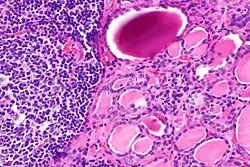

| A micrograph of the thyroid of someone with Hashimoto's thyroiditis | |

Gross morphological changes within the thyroid are seen in the general enlargement, which is far more locally nodular and irregular than more diffuse patterns (such as that of hyperthyroidism). While the capsule is intact and the gland itself is still distinct from surrounding tissue, microscopic examination can provide a more revealing indication of the level of damage.[55] Hypothyroidism is caused by replacement of follicular cells with parenchymatous tissue.[52]

Pathology

Gross pathology of a thyroid with autoimmune thyroiditis may show a symmetrically enlarged thyroid.[5] It is often paler in color, in comparison to normal thyroid tissue, which is reddish-brown.[5]

Microscopic examination (histology) will show lymphocytes (including plasma B-cells) diffusely infiltrating the parenchyma.[55] The lymphocytes are predominately T-lymphocytes with a representation of both CD4+ and CD8+ cells.[5] The plasma cells are polyclonal, with present germinal centers resembling the structure of a lymph node[5] (also called secondary lymphoid follicles, not to be confused with the normally present colloid-filled follicles that constitute the thyroid).[55]

In late stages of the disease, the thyroid may be atrophic.[10] Colloid-filled follicles shrink, and the cuboidal cells that usually line the follicles become Hürthle cells.[5] Fibrous tissue may be found throughout the affected thyroid as well.[5] Severe thyroid atrophy presents often with denser fibrotic bands of collagen that remain within the confines of the thyroid capsule.[55]

Generally, pathological findings of the thyroid are related to the amount of remaining thyroid function — the more infiltration and fibrosis, the less likely a patient will have normal thyroid function.[5] A rare but serious complication is thyroid lymphoma, generally the B-cell type, non-Hodgkin lymphoma.[24]